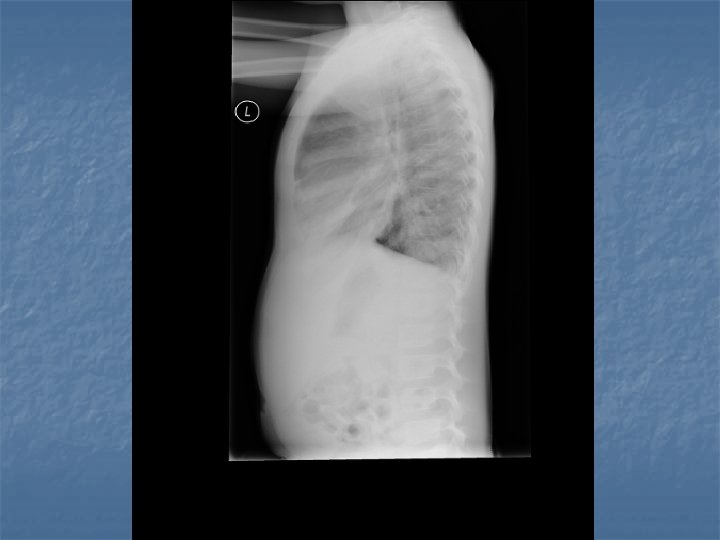

CXR Findings VIRAL n Peribronchial thickening n Diffuse interstitial infiltrates n Hyperinflation BACTERIAL n Subsegmental, segmental or lobar infiltrates n Air bronchograms n Round pneumonia in early S. pneumo n n M. pneumo diffuse infiltrates out of proportion to clinical findings (or bronchopneumonia infiltrates in lower lobes) Bilateral reticulonodular interstitial infitrates

n n n 50% bacterial pneumonia will have lobar infiltrate Can also see alveolar infiltrates Round pneumonia seen with S. pneumo

Blood gases n n n Sa. O 2 <90% or pt has COPD take ABG on room air or baseline 02 level if on chronic O 2 therapy Thoracentesis if effusion >10 mm on lateral XR Recurrent pneumonia – need w/u for immunosupression or structural ab. N